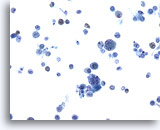

Figure 5

Bronchoalveolar lavage

Oral squamous cells are common in respiratory specimens.

20x

Bronchoalveolar lavage

Oral squamous cells are common in respiratory specimens.

20x